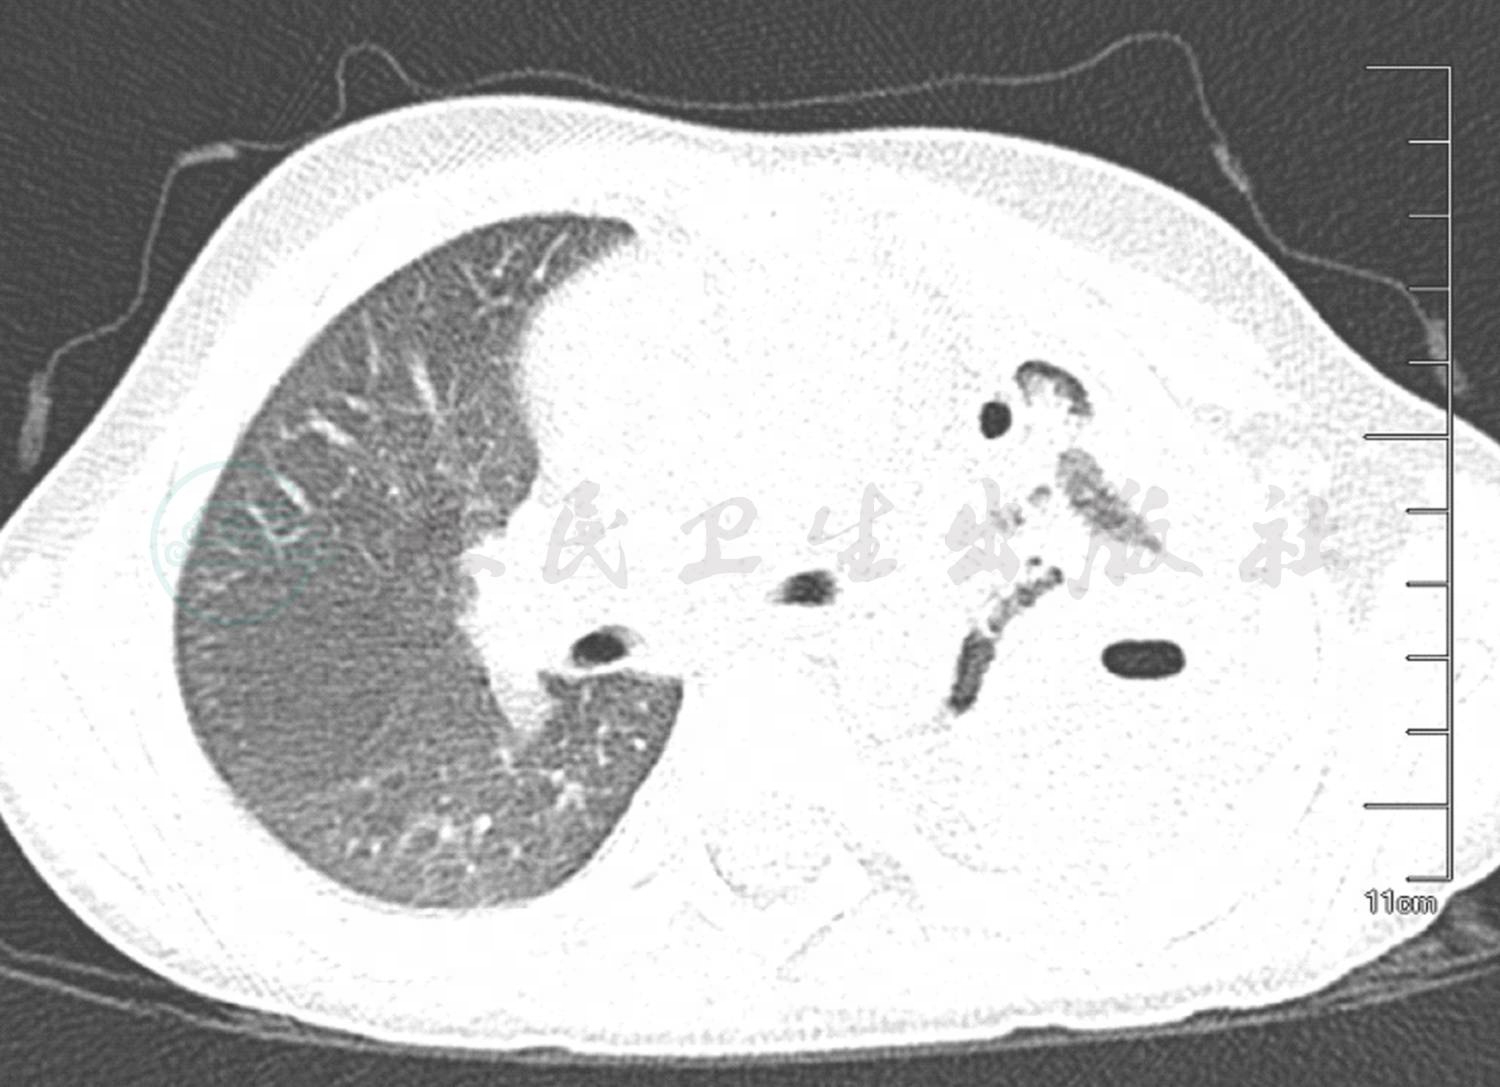

入院后患儿完善彩超定位等各项基础检查后,给予患儿胸腔穿刺术,抽取胸腔积液送化验检查。肺CT回报:左侧胸腔大量积液,伴左肺膨胀不良;右肺散在炎症(图1)。考虑患儿胸腔积液量较大,自行吸收困难,紧急联系外科行胸腔闭式引流。随后在次日胸腔积液的细菌培养中检查到肺炎链球菌生长,药敏结果提示对利奈唑胺敏感,考虑患儿血象高,感染中毒症状明显,该药组织浓度高,穿透性好,随即给予更换该药治疗。于血液检查时发现存在肺炎支原体感染,后给予阿奇霉素联合治疗。另外,患儿血液生化及电解质提示有轻微异常,给予患儿丙种球蛋白、白蛋白等营养支持及维持电解质平衡治疗。经过治疗患儿的体温及感染中毒症状得到了改善,血常规、C反应蛋白等炎症指标均明显下降,但经过10天左右的治疗体温仍有反复,波动在38℃左右。经过病例讨论建议完善纤维支气管镜检查,结果提示支气管内膜损伤较重,有较多分泌物堵塞。结合血液检查中存在肺炎支原体感染,虽然经过大环内酯类药物治疗,仍然不好,可能存在大环内酯类药物耐药,或引发了机体的免疫反应,符合难治性支原体肺炎的诊断,给予患儿静脉滴注甲泼尼龙琥珀酸钠1mg/(kg·次),每天2次,治疗5天,患儿体温逐渐平稳,未再次发热。患儿经过1个多月治疗,体温恢复正常,呼吸平稳,右肺炎症吸收,左肺膨胀及实变好转(图2),出院进行康复治疗。

图2 复查肺CT平扫